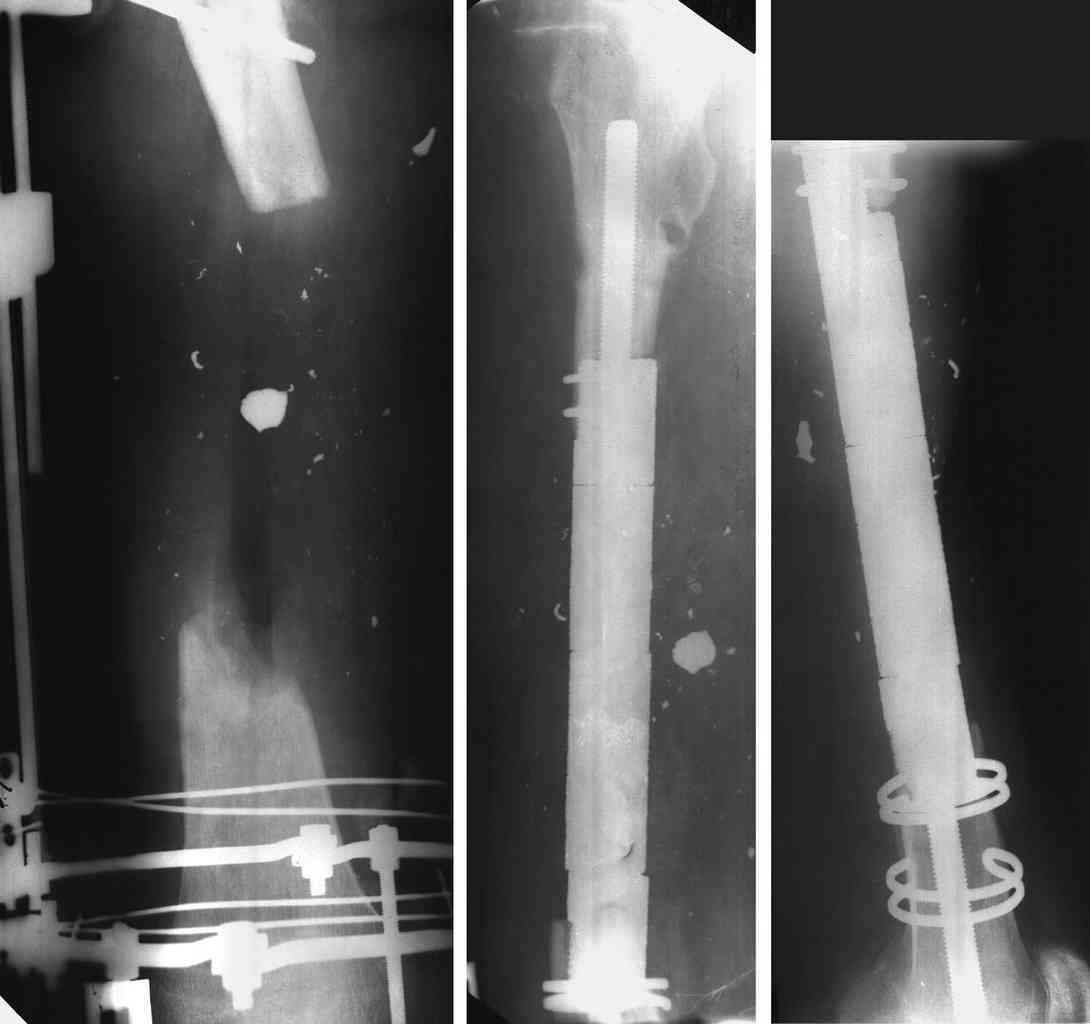

3 Diaphyseal endoprosthesis - see photo (dangerous in soft tissue loss and infection)